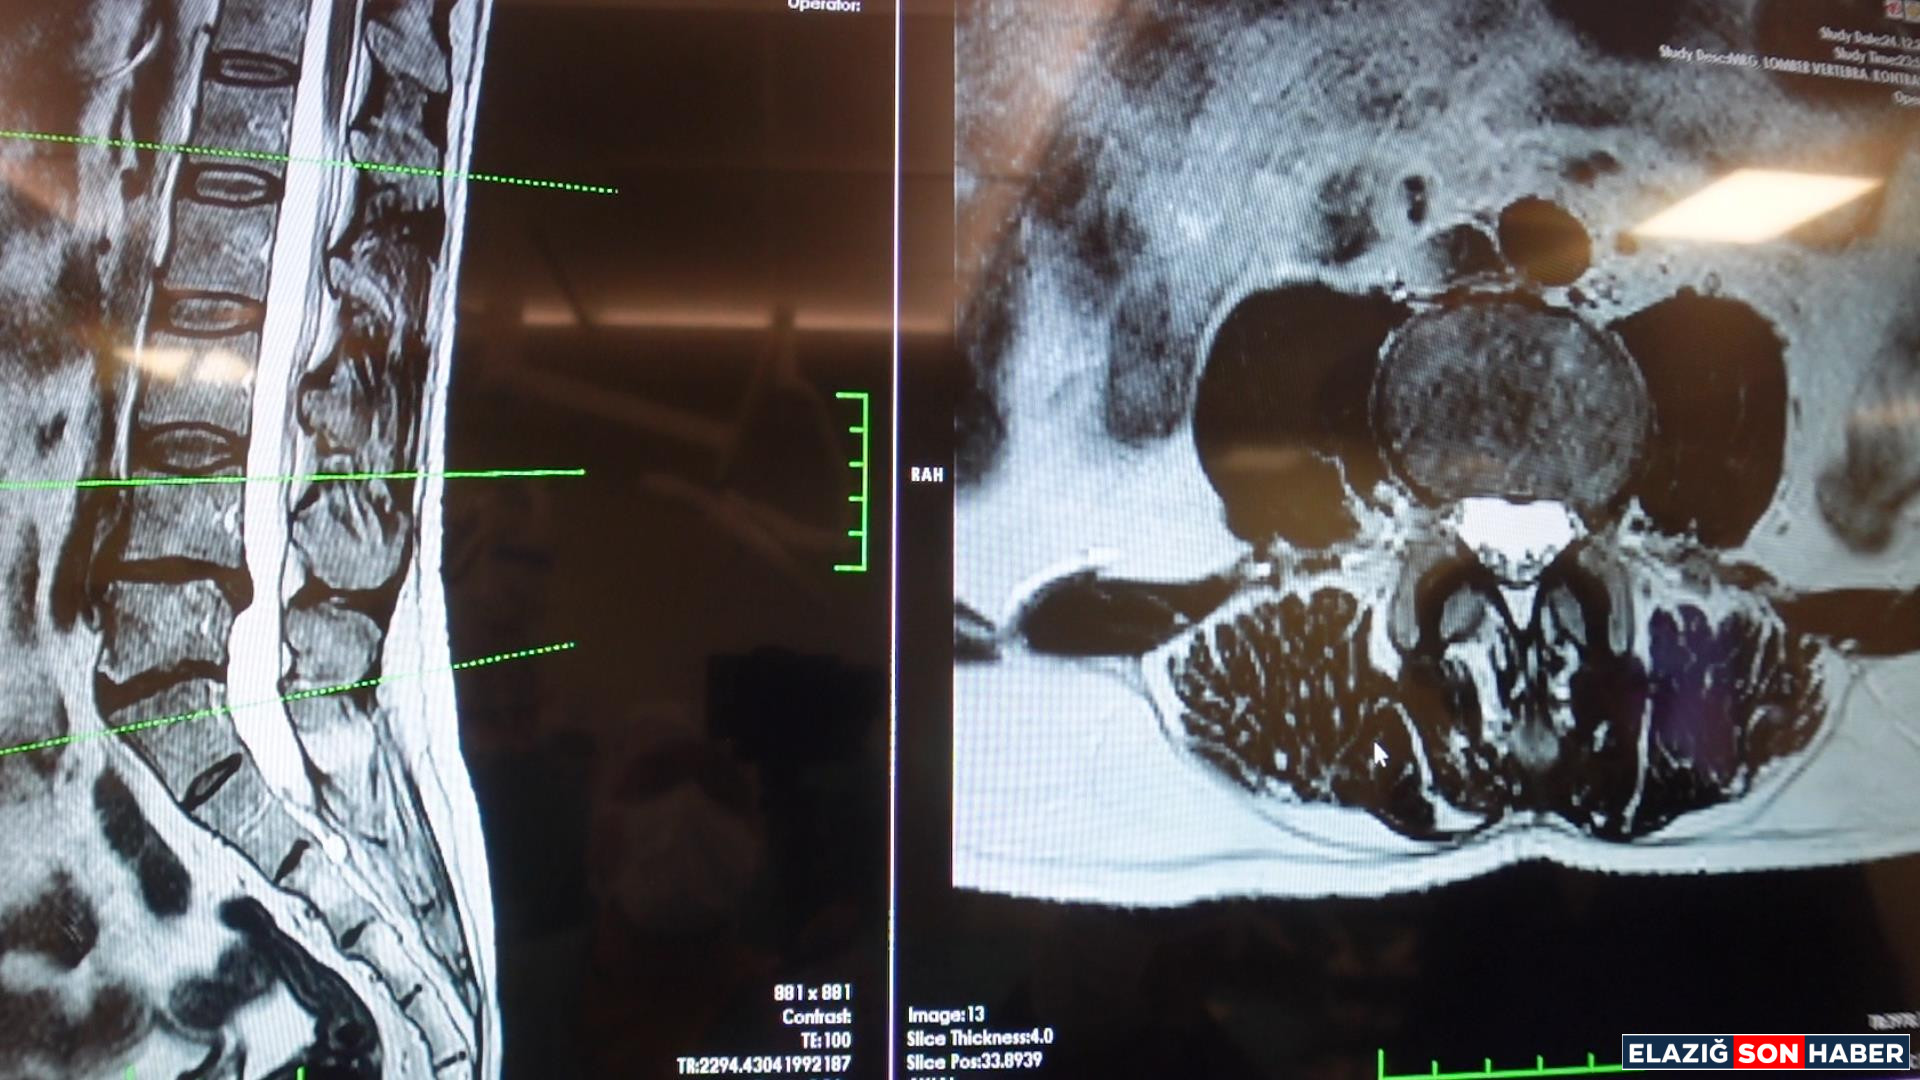

Tedavi sürecinin başarısının tamamen "doğru teşhis" ile mümkün olduğunu vurgulayan Prof. Dr. Fatih Serhat Erol, bel ve bacak ağrısı çeken vatandaşların mutlaka bir Beyin ve Sinir Cerrahisi Uzmanına başvurması gerektiğini hatırlattı. Erol, kapsamlı bir muayene ve gerekli tetkikler (MR, BT vb.) sonucunda hastalıkların birbirinden ayırt edilerek kişiye özel en uygun tedavi planının oluşturulduğunu sözlerine ekledi.